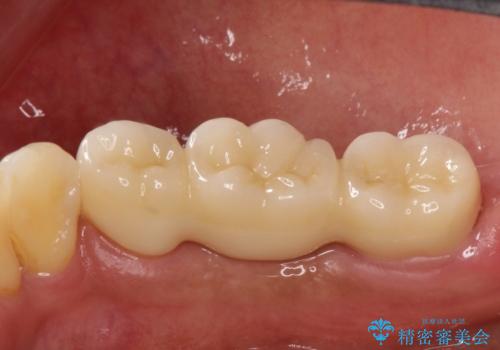

歯根の縦方向への破折は保存不可となることが多いです。

今回は抜歯後、オールセラミックにて修復を行うことで審美性の高い治療を行うことができました。